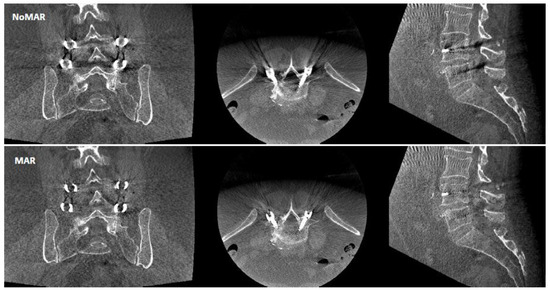

- Grade 0: mild artifact, screw thread clearly visible, cortical bone clearly visible, bone soft tissue interface clearly visible, clear interpretation possible;

- Grade 1: moderate artifact, screw thread visible, cortical bone with unclear portions, bone soft tissue interface distinguishable, interpretation possible;

- Grade 2: strong artifact, screw thread unclear, cortical bone contours unclear, bone soft tissue not distinguishable, interpretation difficult.